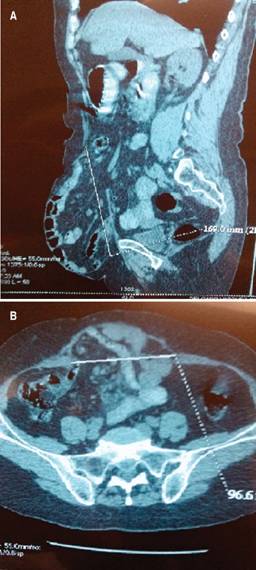

Se realizó un estudio retrospectivo y transversal entre agosto de 2016 y enero de 2018 en dos hospitales del sector público; el Hospital General 450 de Durango, Dgo. y el Hospital General de Zona Núm. 16 del IMSS en Torreón, Coah. Se tomaron en cuenta los siguientes criterios: pacientes mayores de 18 años, ambos sexos, con hernias ventrales o inguinales que a la exploración física presentaran hernias con sacos herniarios de tamaño gigante (Figura 1) catalogados como hernia con pérdida de dominio y defectos herniarios gigantes, entendiendo este concepto como aquellas hernias mayores de 10 cm de diámetro del defecto (Chevrel5) y cuyo contenido excede la capacidad de la cavidad abdominal.6 Como criterios de exclusión se establecieron: pacientes con patologías psiquiátricas. Pacientes que no aceptaron participar en el protocolo de estudio.

Figura 1: A y B. Imagen tomográfica de una paciente con hernia gigante sin pérdida de dominio. Se ven las medidas del defecto herniario.